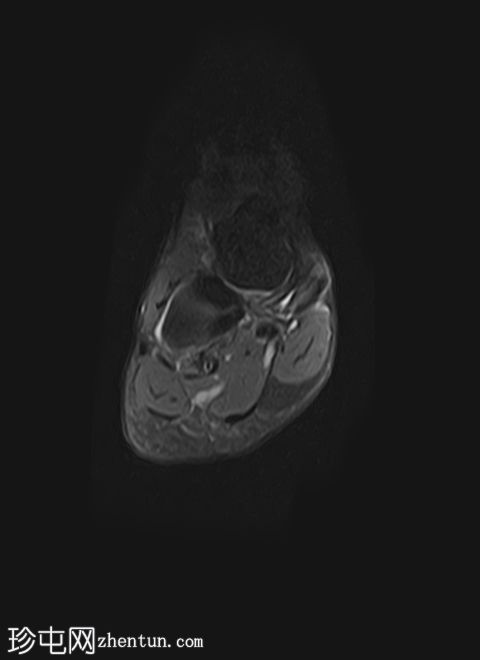

冠状位脂肪抑制

T1加权像

质子密度(PD)脂肪抑制像显示第二跖骨干骨髓水肿,伴骨膜及周围软组织水肿。未见明确的皮质骨折线。

第二跖骨应力性骨折,根据Fredericson分级,MRI分级为3级,伴骨膜及周围软组织水肿。